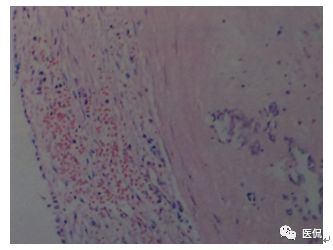

病理诊断

行全麻鼻内镜下唇龈沟双径路左上颌窦肿物摘除术。病理:鼻粘膜慢性活动性炎,间质广泛陈旧性出血,血肿形成、机化、钙化,纤维组织明显增生、包绕。

左上颌窦出血坏死性息肉。

出血坏死性息肉临床上较少见,是一种以出血坏死为特征的特殊类型的慢性上颌窦或(和)鼻腔炎症,组织学上常表现为以血管增生坏死为主的血管息肉,部分为水肿型、腺体型或纤维型,间质内有较多的慢性炎症细胞浸润,局部有坏死组织及陈旧性血块。其发病原因和机制尚不明确,有人认为窦腔内有息肉存在,因息肉扭转使静脉回流障碍,血管内压增高,导致息肉损伤及其血管破裂出血,用力抠鼻及外伤等因素导致本病的可能性较大。本病发病年龄以青壮年居多,临床主要症状为鼻塞、鼻出血或涕中带血,病灶较大时可引起面部畸形,眼球突出。好发于上颌窦及鼻腔,其他鼻窦亦可累及。